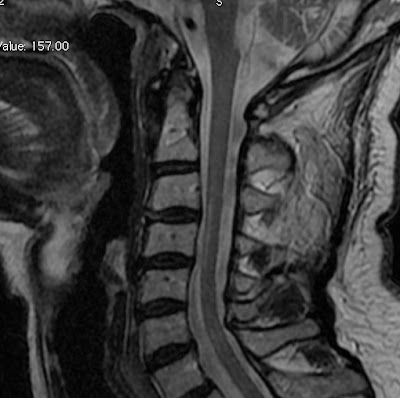

The Role Of MRI In The diagnosis Of Multiple Sclerosis

1 The role of MRI in the diagnosis of Multiple Sclerosis LH is a 34 yo female with a history of relapsing remitting MS presents to the multiple sclerosis clinic ... Document Retrieval